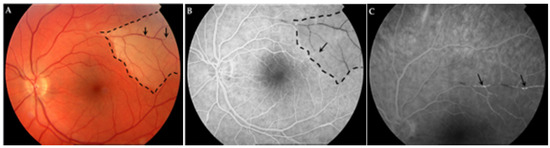

| Retinal fluorescein angiography | Bilateral BRAO | Unilateral BRAO with infarction and bilateral vasculitis | Unilateral BRAO a, bilateral peripheral retinal non-perfusion | Bilateral BRAO with infarction | Bilateral peripheral retinal non-perfusion with unilateral vasculitis | Bilateral BRAO with infarction and vasculitis | Bilateral BRAO with infarction | Normal | BRAO with vasculitis |